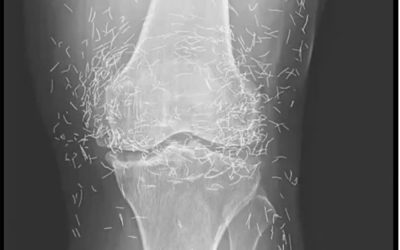

X-Ray Reveals Hundreds of Gold Needles in Woman’s Knees

As doctors examined an X-ray image of the knees of an old woman experiencing severe joint pain, they found a…